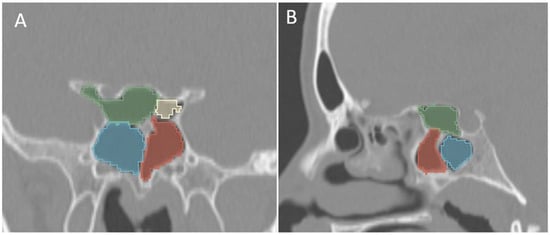

Figure 6.

Coronal (A) and sagittal (B) reformatted CT images of a 13-year-old boy with bilateral Onodi cells (green and yellow) above the sphenoid sinuses (blue and red).

Additionally, the images were assessed for the presence of anatomic variants of the nasal cavity and PNS. Sinonasal variations were defined based on the European Position Paper on the Anatomical Terminology of the Internal Nose and Paranasal Sinuses [19]. According to this paper, the maxillary sinus is located between the orbital floor and alveolar process of the maxilla; the sphenoid sinus is the pneumatization of the sphenoid bone posterior to the rostrum; and the frontal sinus is defined as the pneumatization superior to a noticeable frontal beak [11,19]. The ANs are defined as the aeration of the protuberance on the lateral nasal wall, slightly anterior to the middle turbinate attachment (Figure 4). The Haller cell is an ethmoidal air cell, located below the orbital floor and lateral to a line parallel with the lamina papyracea (Figure 5). Onodi cell is the posteriorly located ethmoidal cell which develops just above and lateral to the sphenoid sinus (Figure 6). Concha bullosa is the pneumatization of the vertical segment of the middle turbinate (Figure 7) [19]. All anatomical variants were initially assessed by a single radiologist with four years of experience in maxillofacial CT imaging, who was blinded to patients’ demographic data, including age and sex. All assessments were done on a DICOM viewer (Medixant. RadiAnt DICOM Viewer [Software]. Version 2024.1. URL: https://www.radiantviewer.com (accessed on 1 November 2024)), after retrieval from the hospital PACS system to provide anonymized evaluation. The prevalence of each variant and the frequency of its bilaterality in each group were recorded. The evaluations were subsequently reviewed by a second radiologist with 11 years of experience. In cases of uncertainty regarding the presence of anatomical variations, a consensus decision was reached in consultation with a third radiologist with 13 years of experience.

Similarly, since Onodi cells are typically observed after the age of five and their frequency stabilizes in late childhood, the comparison of sphenoid sinus volumes was performed in patients older than eight years. In this group, the mean right sphenoid sinus volume was 4.47 ± 2.53 cm3 in cases with Onodi cells (n = 17) and 3.79 ± 2.18 cm3 in those without (n = 63; p = 0.268). On the left, the mean sphenoid sinus volume was 5.01 ± 2.02 cm3 with Onodi cells (n = 19) and 4.32 ± 2.15 cm3 without (n = 61; p = 0.223).

Haller cells were more frequently identified after the first year of life, whereas Onodi cells tended to appear after the age of five, though their prevalence remained lower than that of other ethmoidal cell variants in older age groups. Similarly to sinus volumes, no significant difference in the prevalence of these anatomic variations was found between male and female patients. Awareness and preoperative identification of Haller and Onodi cells are crucial for surgical planning, as their presence may increase the risk of intraoperative complications [24]. Haller cells, located near the maxillary sinus ostium or the hiatus semilunaris, are associated with a higher risk of orbital injury during ethmoidectomy, while Onodi cells—also known as sphenoethmoidal cells—are situated close to the sphenoid sinus recess and have been linked to optic nerve or internal carotid artery injury during functional endoscopic sinus surgery (FESS) or transsphenoidal procedures [7,24]. Interestingly, the emergence of Onodi cells in parallel with sphenoid sinus pneumatization suggests that, although traditionally classified as posterior ethmoidal cells, they may in fact originate from the sphenoid sinus itself. Despite their anatomical proximity to the drainage pathways of the maxillary and sphenoid sinuses, respectively, our findings demonstrated that the presence of Haller cells did not significantly influence maxillary sinus volume, nor did Onodi cells affect sphenoid sinus volume in the pediatric population.